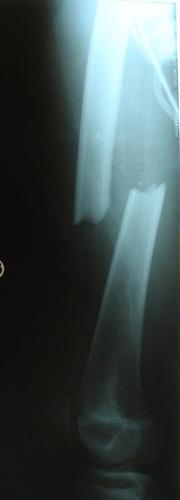

Fracture du fémur – Enclouage centro-médullaire

Chez le grand enfant, la fracture de fémur peut être traitée par un enclouage centro-médullaire qui apporte plus de stabilité à la fracture.

Ce traitement est possible à partir de 11-12 ans chez la fille et 13-14 ans chez le garçon.